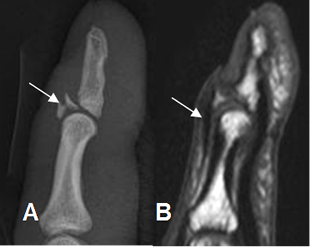

Fig 63. Dedo en martillo.

A: Rx lateral. Avulsión sobre la inserción del tendón extensor, en la base en la falange distal.

B: RM sagital en T1. Se confirma la avulsión. El tendón extensor se aprecia íntegro.